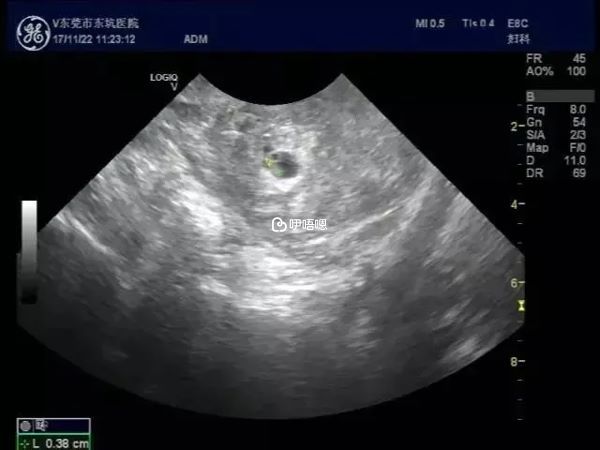

2013年4月8號:B超確定雙胞胎,資料看下圖。

2013年5月3號:B超回來,雙胎大小差不多,資料看圖,生殖中心說已畢業,下次不用去她那邊了,直接轉產科,好開心!